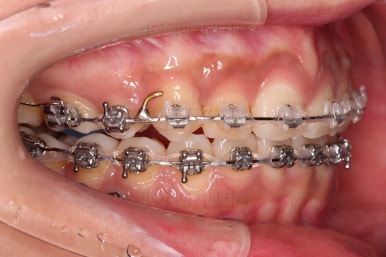

윗니는 이 뽑은 자리를 줄여나가고요.

아랫니는 어금니와 사랑니를 앞으로 당겨옵니다.

물론 다른 치아에 변화를 주지 않기 위해서 미니스크류를 이용합니다.

큰 틀에서는 잘 진행 중인 것 같지만 이번 경우처럼 윗니만 발치, 그리고 발치 위치가 다른 경우, 더군다나 아랫니도 어금니가 없고 사랑니를 당겨오는 경우.

미세한 치아 크기 차이로 마지막 마무리가 오래 걸리는 경우가 많습니다.

100% 중앙선이 잘 안맞는 경우가 많고 미세한 틈새가 오랫동안 잘 안닫히기도 합니다.

이번 환자분도 마찬가지로 중앙선이 100% 안맞았고, 틈새를 타이트하게 닫기 위해 시간이 좀 소요되었습니다.